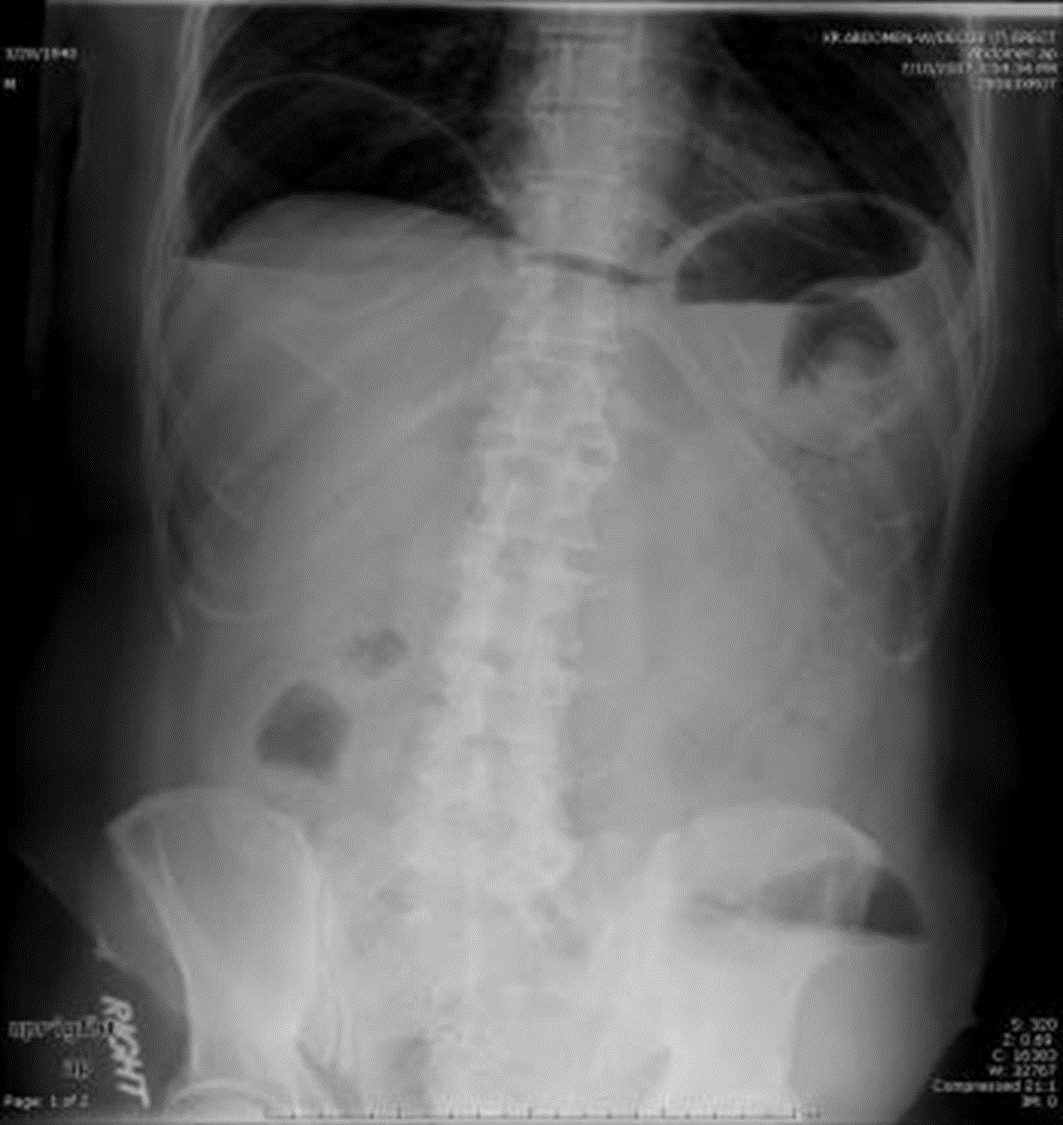

Loét tá tràng

image